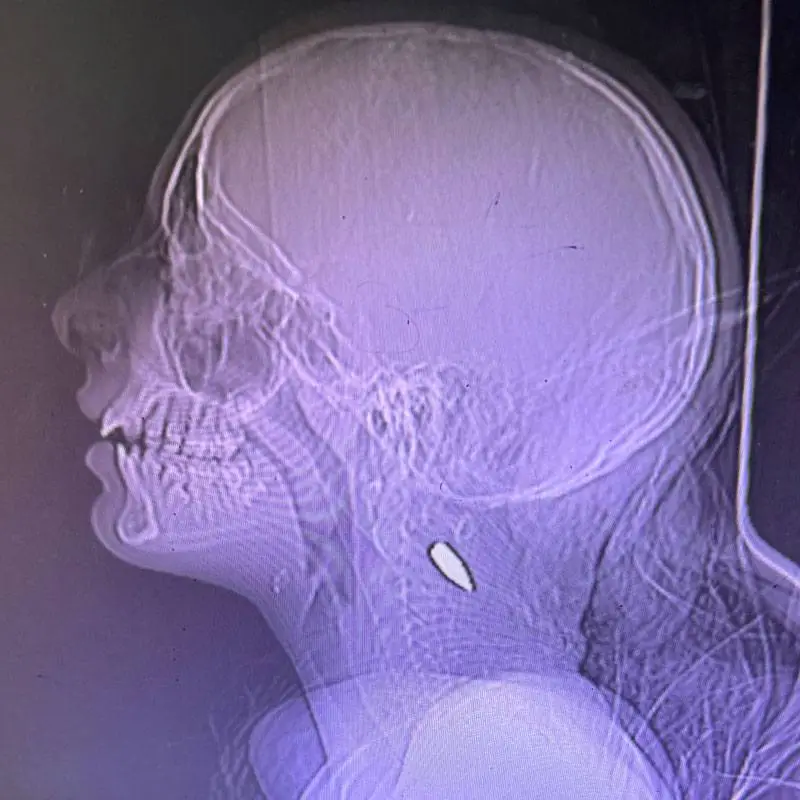

View attachment 1058167